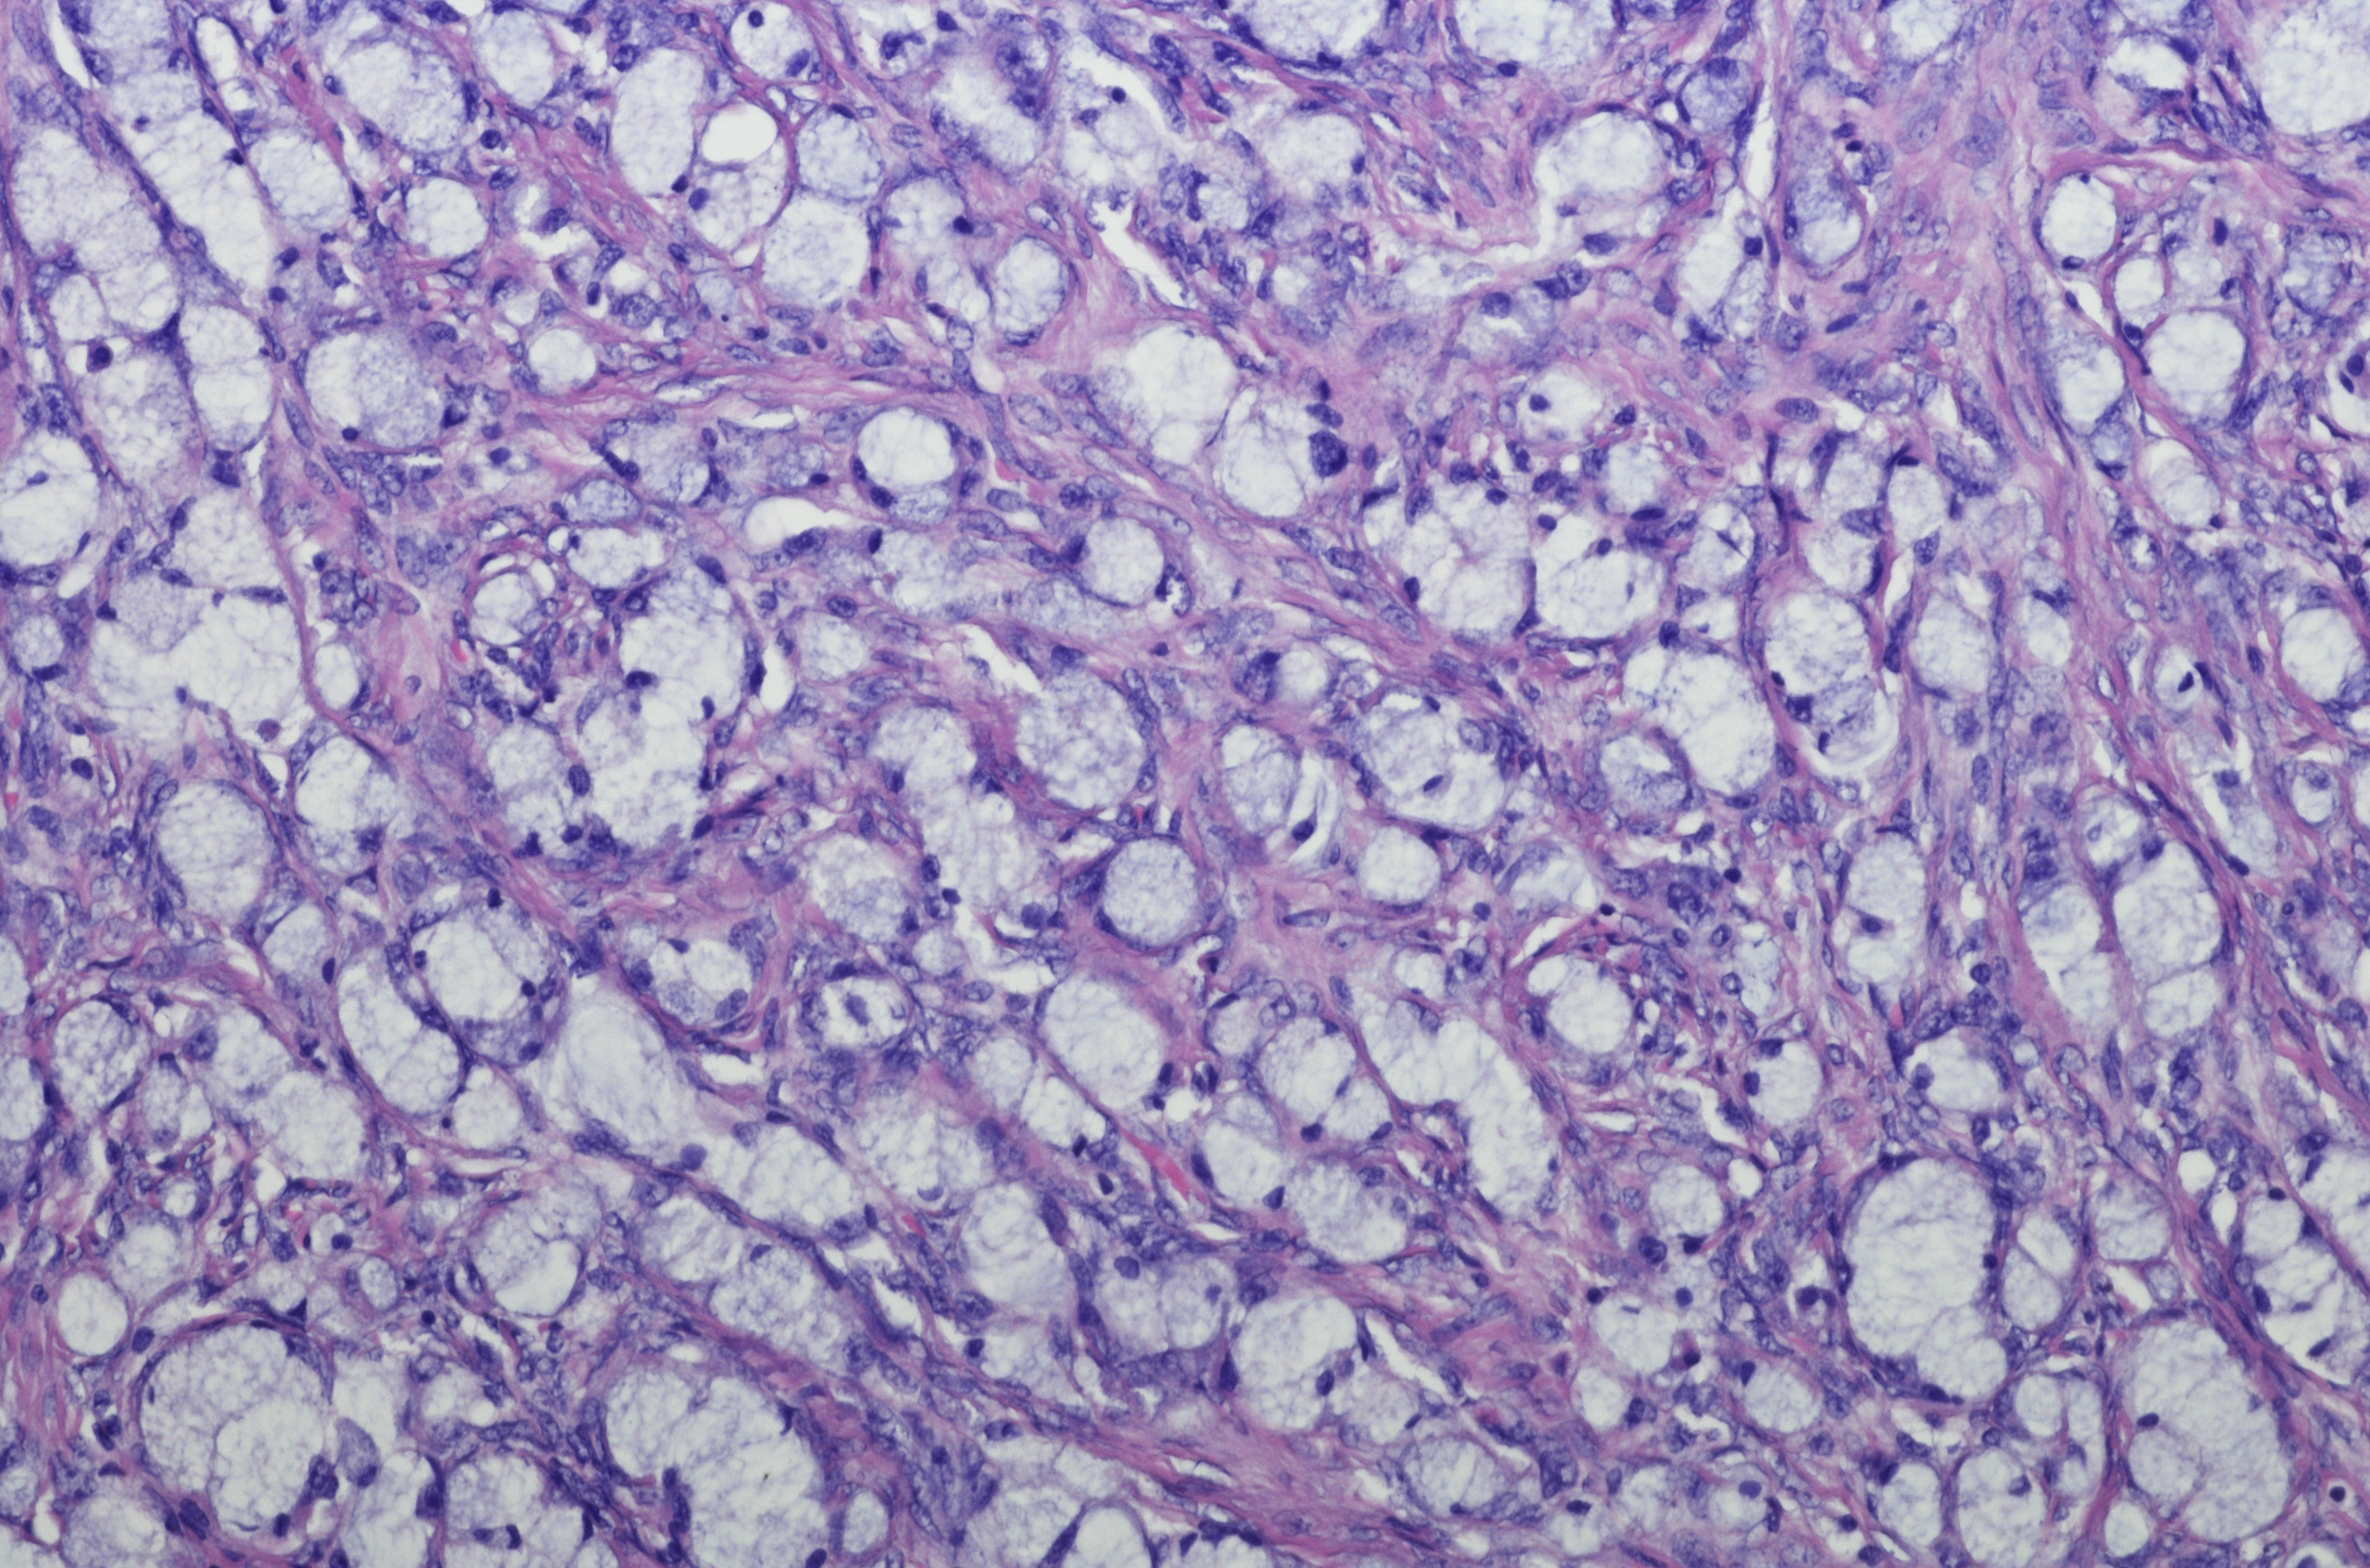

Improving global kidney health by understanding kidney disease

Our work identifies and understands the incidence, prevalence and history of kidney disease at a population level so we can find solutions and treatments.

In collaboration with Royal Prince Alfred Hospital, we aim to identify and understand the incidence, prevalence and history of kidney disease at a population level. Through this work, we seek to find solutions and treatments for kidney disease including: